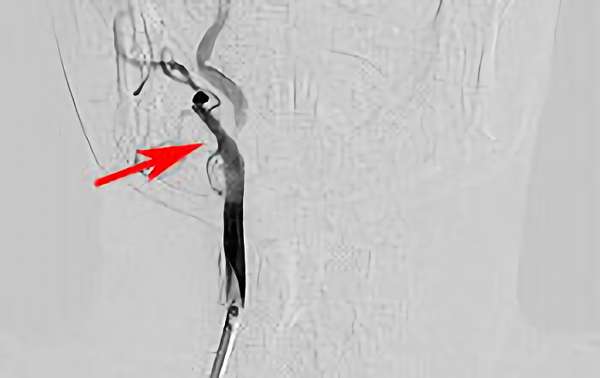

'18年6月

左椎骨動脈瘤

80代

大阪府の病院

No.163 手術前

No.163 手術中

No.163 手術後